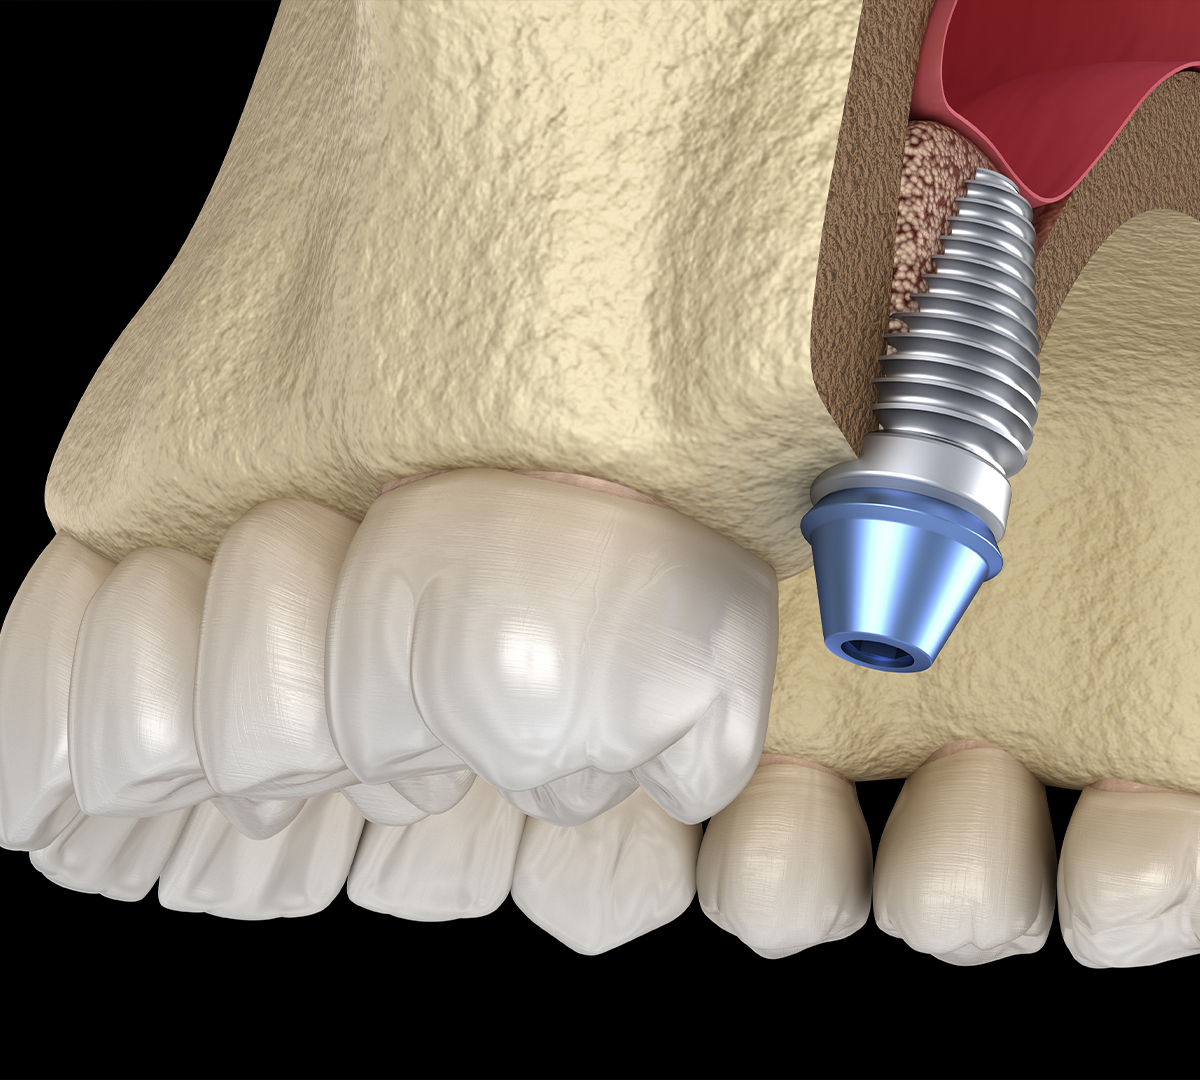

La chirurgie du sinus, aussi appelée Sinus Lift ou élévation du plancher sinusien, est une intervention visant à augmenter le volume osseux nécessaire à la pose d’implants dentaires.

Le sinus maxillaire est une cavité aérienne située au-dessus des prémolaires et molaires supérieures. Son rôle est d’humidifier et filtrer l’air respiré. Cependant, lorsqu’une dent est extraite, l’os qui la supportait peut progressivement perdre en volume et en densité, rendant la pose d’un implant difficile, voire impossible.

L’élévation du plancher sinusien permet d’ajouter une greffe osseuse sous la membrane du sinus afin d’augmenter la hauteur d’os et de créer un support solide pour un implant dentaire.

- Une incision est pratiquée pour accéder au plancher sinusien.

- Le sinus est délicatement soulevé, et une greffe osseuse est insérée pour augmenter la densité osseuse.

- Une fois la greffe en place, la gencive est refermée avec des sutures.

Après 4 à 9 mois de cicatrisation, l’os greffé se consolide, permettant ainsi la pose des implants dentaires en toute sécurité.